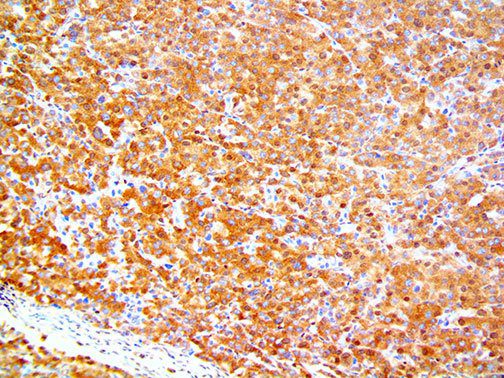

It is the ICU physician who is most likely to witness one of the deadliest manifestations of the abnormal immunological response, the cytokine storm syndrome (CSS). This response is also referred to by some as the cytokine release syndrome (CRS). CSS is characterized by continuous activation and expansion of macrophage and lymphocyte populations, which secrete large amounts of cytokines, causing the cytokine storm. This massive cytokine release is akin to hemophagocytic lymphohistiocytosis (HLH) disease, a syndrome characterized by initial unchecked and persistent activation of cytotoxic T lymphocytes and NK cells.

Clinical and laboratory manifestations of HLH include fever, enlarged liver and/or spleen, neurologic dysfunction, coagulopathy, liver dysfunction, cytopenias (i.e., low levels of erythrocytes, leukocytes, and/or platelets), hypertriglyceridemia, hyperferritinemia, hemophagocytosis, and eventually diminished NK cell activity as the immune system becomes progressively paralyzed. HLH can be familial (primary HLH) or secondary to another disease process (sHLH), such as rheumatic disease, in which it is referred to as macrophage activation syndrome (MAS, characterized by elevated ferritin).